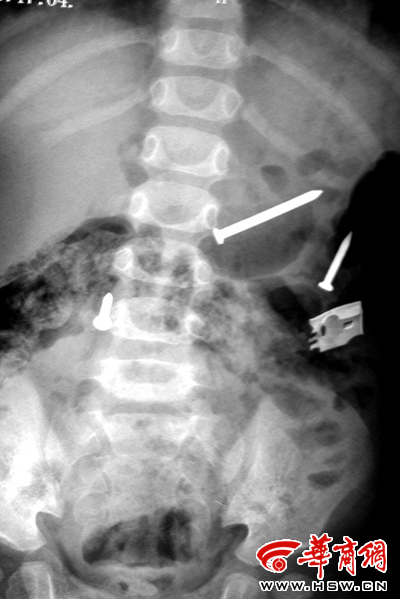

排出鐵釘之后復檢拍片又顯示肚內有鐵釘(劉立春攝)

來自榆林市米脂縣的這名一歲半女孩,在最近一個多月內,從體內不斷排出鐵釘,共達20多枚。更為奇怪的是,在醫院拍片顯示體內已沒有鐵釘時,過幾天鐵釘還會出現。